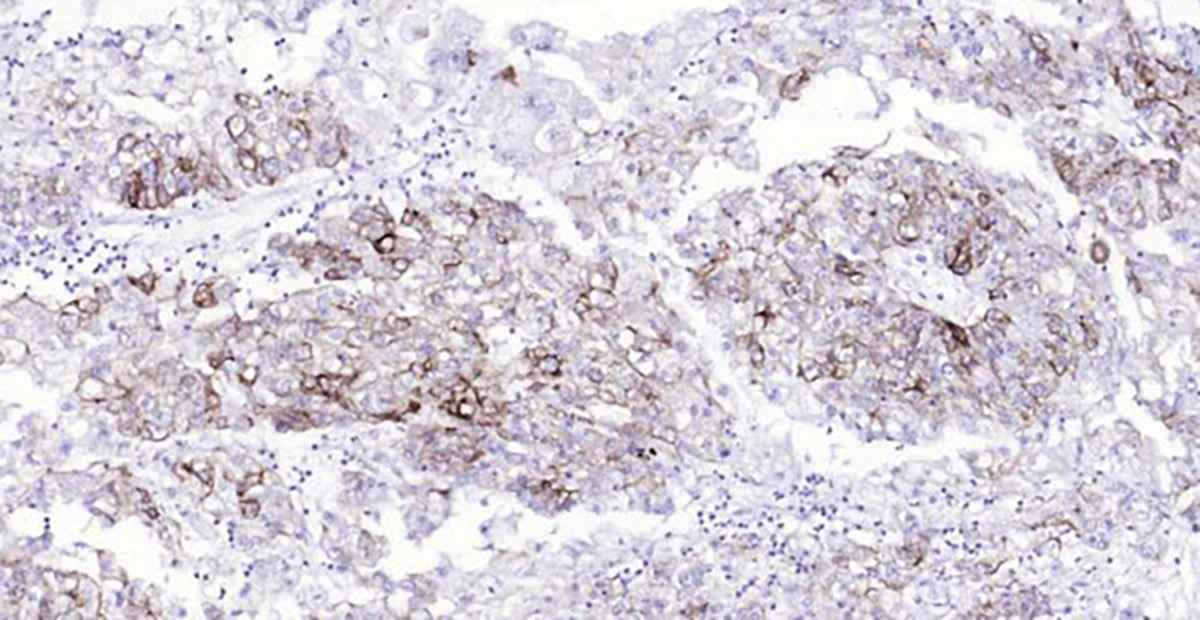

Bioss Ready-To-Use

IHC Kits

Perfect for quickly and conveniently obtaining high-quality IHC data. These kits contain all the needed reagents, primary and secondary antibodies, AND a positive control slide to confirm your staining.

With our optimized protocol, simply use the reagents directly on your tissue sample, and you are ready to gather your data for analysis.